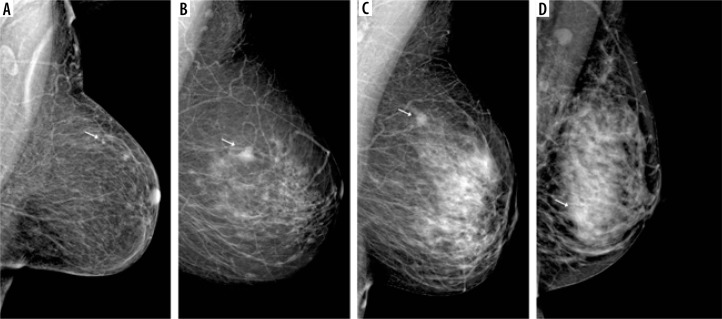

Purpose: To assess the effectiveness of contrast-enhanced mammography (CEM) recombinant images in detecting malignant lesions in patients with extremely dense breasts compared to the all-densities population.

Material and methods: 792 patients with 808 breast lesions, in whom the final decision on core-needle biopsy was made based on CEM, and who received the result of histopathological examination, were qualified for a single-centre, retrospective study. Patient electronic records and imaging examinations were reviewed to establish demographics, clinical and imaging findings, and histopathology results. The CEM images were reassessed and assigned to the appropriate American College of Radiology (ACR) density categories.

Results: Extremely dense breasts were present in 86 (10.9%) patients. Histopathological examination confirmed the presence of malignant lesions in 52.6% of cases in the entire group of patients and 43% in the group of extremely dense breasts. CEM incorrectly classified the lesion as false negative in 16/425 (3.8%) cases for the whole group, and in 1/37 (2.7%) cases for extremely dense breasts. The sensitivity of CEM for the group of all patients was 96.2%, specificity - 60%, positive predictive values (PPV) - 72.8%, and negative predictive values (NPV) - 93.5%. In the group of patients with extremely dense breasts, the sensitivity of the method was 97.3%, specificity - 59.2%, PPV - 64.3%, and NPV - 96.7%.

Conclusions: CEM is characterised by high sensitivity and NPV in detecting malignant lesions regardless of the type of breast density. In patients with extremely dense breasts, CEM could serve as a complementary or additional examination in the absence or low availability of MRI.